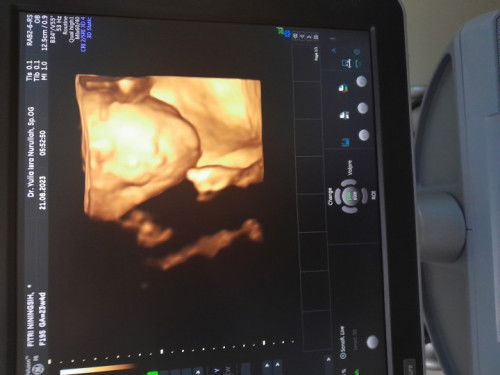

Hasil usg 24 minggu

Baca lagiitu yang nampak cuma usia kehamilannya aja 23 minggu 4 hari, fotonya kurang full bun, biasanya ada penjelasannya di samping gambar berupa singkatan kata, Dan kalo dokternya diem biasanya berarti semuanya normal huhu tp aku juga greget sama dokter yang mingkem gitu.

Baca lagiitu sih kalo saya liat digambarnya ada hidung bibir mata lengkap, normal normal saja bun. tapi kalo nanti usg lagi lebih baik ditanyakan langsung sama dokternya gimana kesehatan janinnya ya bun.